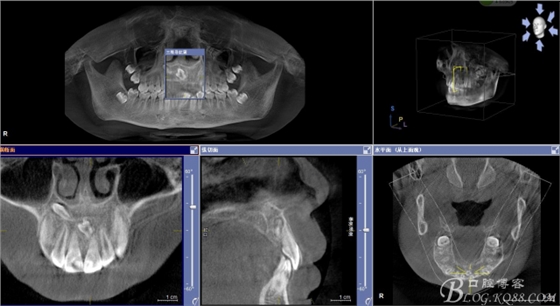

患者、男、15歲,主訴:牙齒不整齊,要求正畸治療。??茩z查:見圖1 ,cbct檢查:11與21之間,12與13之間各有異倒置多生牙,尤其以21根尖區(qū)多生牙位置高,與患者家屬充分溝通,患者同意拔除兩顆多生牙。簽知情同意書。

圖1.術(shù)前正畸科的病歷圖片:建議拔除12根方接近鼻底的多生牙及11、21根方倒置多生牙

圖2.cbct影像檢查:11與21之間有一倒置多生牙。